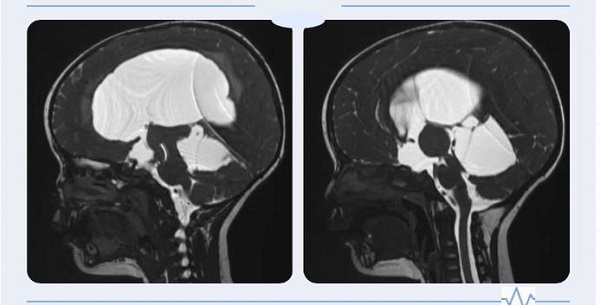

一岁多的赫赫自出生头颅就比同龄小孩大,近半月来进食后出现呕吐、头痛,哭闹不止,在省内多处求医未果,最终慕名来到陕健医二一五医院神外重症监护室就诊,行磁共振检查后诊断为“梗阻性脑积水”。